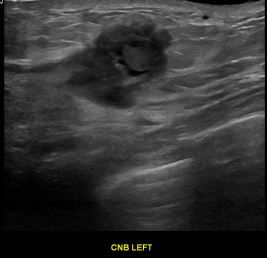

상기환자는 만져지는 멍울있어 검사위해  내원하신 40대 초반

여성분으로 의심스러운 좌측유방혹 조직검사 시행해 유방암으로 진단되었습니다